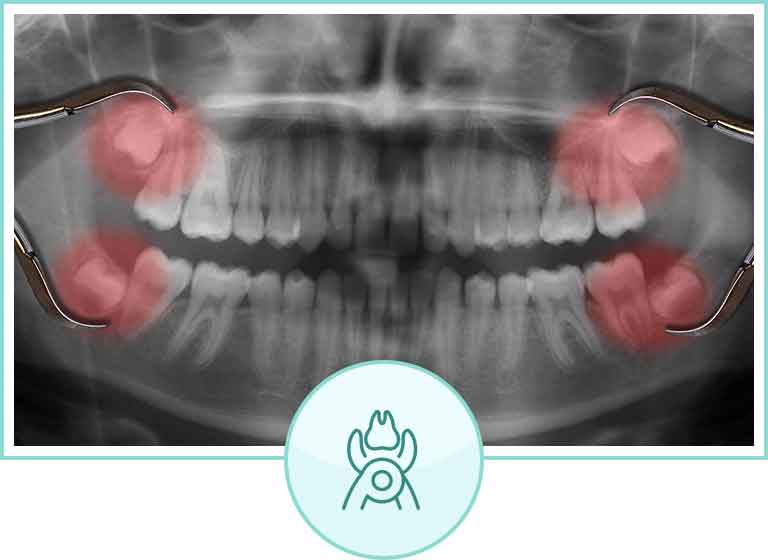

親知らずの治療

トラブルを起こす可能性が高い親知らずも、早めの抜歯でトラブルを未然に防げます

親知らずは、正式には「第3大臼歯」や「智歯」と呼ばれており、だいたい思春期以降に生え始めますが、30代以降に生えてくる人もいます。ですが全ての人に生えるというわけではなく、埋まって出てこない人もいれば、もともと親知らずが備わっていない、という人もいます。

親知らずは必ずしも抜かなければならないものではなく、トラブルを起こす原因になる場合にのみ抜歯が勧められます。

親知らずを抜くのをおすすめする場合

中途半端に埋もれている場合

親知らずが正しく埋まっておらず、まともに生えてこない場合、放っておくと虫歯や歯周病を引き起こしてのちにトラブルを招く可能性が高いため、できるだけ早めに抜歯をするのがおすすめです。

虫歯や歯周病になっている場合

親知らずはかなり奥に位置していますので、歯磨きがしにくく、虫歯や歯周病を起こすことが少なくありません。すでに虫歯や歯周病にかかってしまっている場合、放っておくと悪化してしまう可能性が非常に高いため、痛みが出る前に抜いた方が良いでしょう。

顎関節症や口内炎の原因になっている場合

親知らずの生える方向によっては、顎関節症や口内炎の原因になることがあります。このようなケースでもトラブルに悩まされ続けるのを避けるために、抜歯をおすすめします。

歯並びを乱す原因になっている場合

特に、親知らずが斜めや横向きに埋まっている場合、手前の歯を押して歯並びが乱れてしまう原因になることがあるため、放置はおすすめしません。